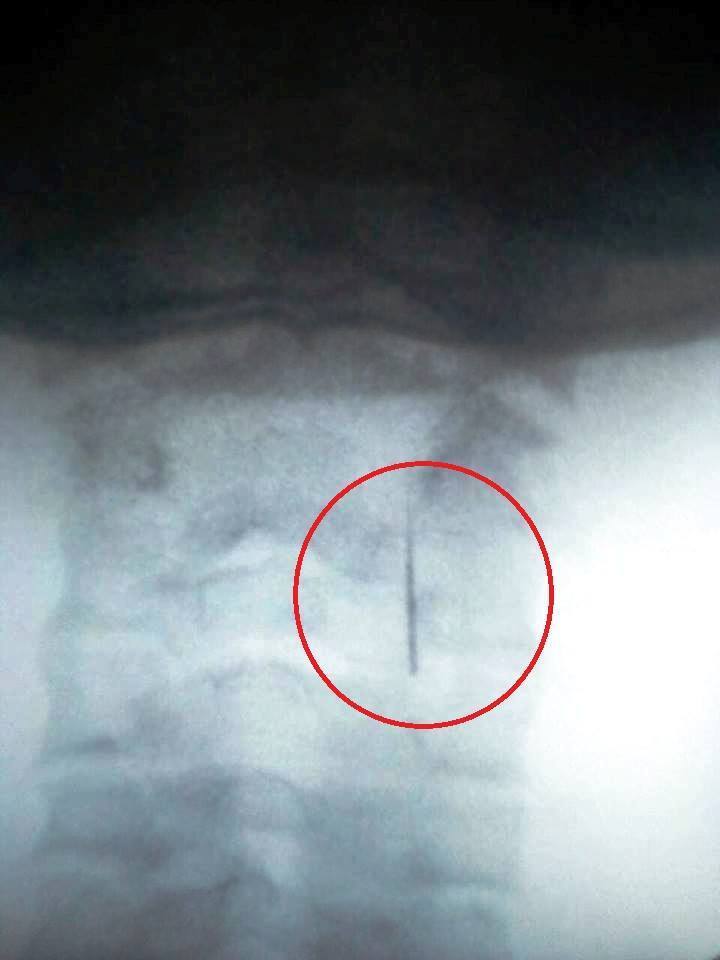

Матір і дитину відправляли з лікарні в лікарню, і тільки в одній із поліклінік Ужгорода вдалося зробити рентген-знімок, після чого голку таки витягли.

“Рентгенолог побачив у горлі голку! Він єдиний з усіх лікарів, нарешті, виписав перший змістовний медичний документ, віддав мамі і негайно відправив в обласну лікарню”, — зазначила Приходько.